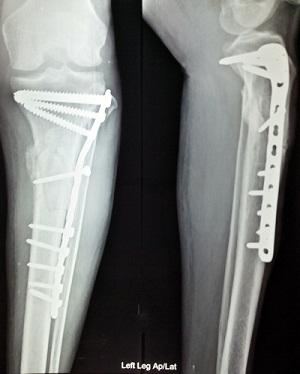

·         Internal Fixation Devices

o    Screws and Plates

o    Intramedullary Rods and Nails

o    Fracture Fixation Devices

§  Tibial Fracture Fixation Devices